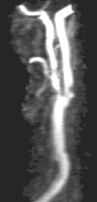

CE-MRA of the aortic arch and great vessels (left) into the brain, renal arteries (top), selective carotid bifurcation (top right) showing ICA/ECA stenosis, and 3-section run-off (very right) showing multiple stenoses, including long-segment bilateral SFA stenoses.

CE-MRA is a fairly new, non-invasive MR technique that utilizes ultra fast MR sequences to obtain exquisite MRA images. These images are obtained during intravenous administration of only 20-30 cc of Gadolinium using an MR-compatible power injector. A bolus-tracking software tracks the bolus of contrast for optimal timing. Subtraction techniques may also be utilized for improved tissue contrast. Thus, a high-end scanner is required to perform the procedure.

Carotids, brain, aorta, renals, pulmonary, run off, etc.